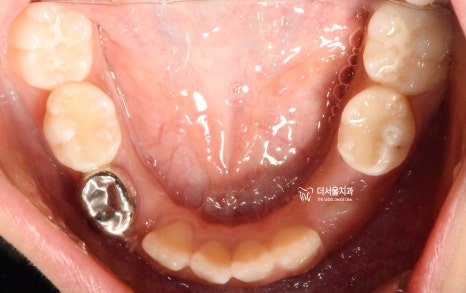

『구강 내 사진』

성장교정 이 필요한 이유는,

구강 내 사진에서도 뚜렷히 찾아볼 수 있습니다.

유치가 빠지면서 영구치아가 올라오고 있는

혼합치열기에서, 영구치가 올라올 수 있는

충분한 공간을 확보하면서

턱의 위치를 바로 잡는것이 핵심포인트입니다.

우선 여기서 봐야 될 큰 문제는

1) 절단교합(Edge to edge bite) 입니다.

윗니가 아랫니를 물고 있어야 되는데,

서로 절단연끼리 맞닿고 있죠.